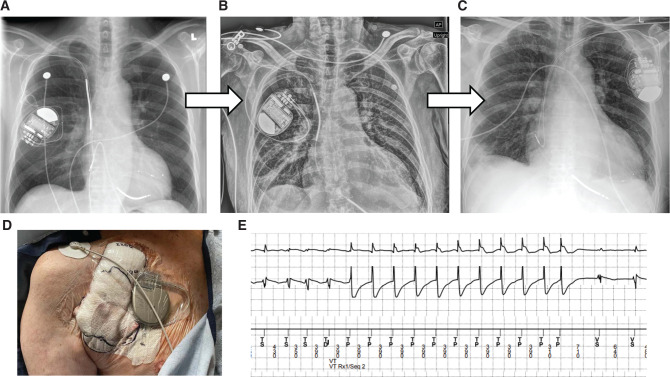

随着心脏植入式电子设备(CIED)治疗应用的不断扩大,血管内设备感染变得越来越常见。在经静脉植入式心律转复除颤器(ICD)感染需要拔除以清除细菌的情况下,目前仍没有标准方法在设备拔除后提供临时 ICD 治疗。我们介绍了一例持续性菌血症并发单形室速(VT)电风暴的病例,在该病例中,我们对双心室 ICD 系统进行了摘除,并在重新植入新的永久性系统之前,使用带有外置 ICD 发生器的临时经静脉双线圈导联治疗 VT 发作。该病例证明了临时外置经静脉 ICD 系统在成功检测和终止 VT 方面的作用,从而减少了在治疗 CIED 感染期间外部除颤器冲击带来的痛苦和潜在危害。

With the expanding use of cardiac implantable electronic device (CIED) therapy, intravascular device infections are becoming more common. In the case of transvenous implantable cardioverter-defibrillator (ICD) infections requiring extraction for bacterial clearance, there remains no standard method to deliver temporary ICD therapy following device removal. We present a case of persistent bacteremia complicated by monomorphic ventricular tachycardia (VT) electrical storm where biventricular ICD system extraction was performed and a temporary transvenous dual-coil lead with an externalized ICD generator was used to treat VT episodes prior to the re-implantation of a new permanent system. This case demonstrates the utility of a temporary externalized transvenous ICD system in the successful detection and pace-termination of VT, thereby reducing episodes of painful and potentially harmful external defibrillator shocks during the treatment of CIED infection.